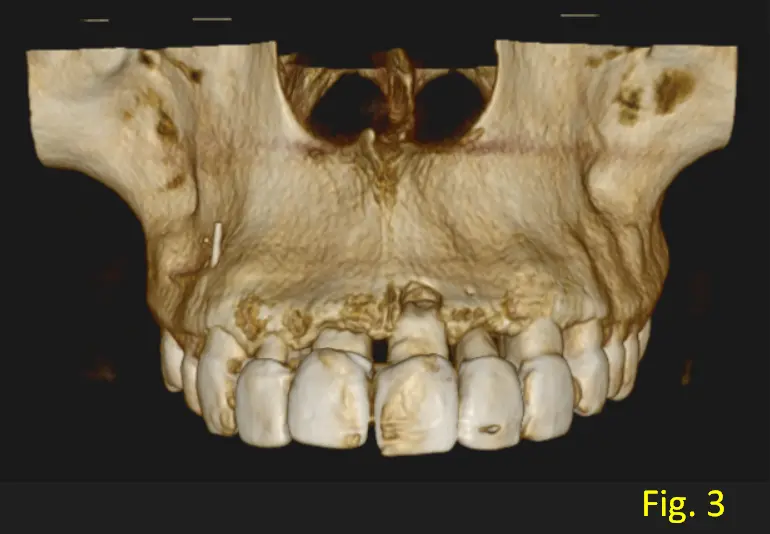

Ademas se observa a la pieza dentaria 1.4 con tratamiento de conducto, lesión periapical en su raiz mesial y en la Fig. 3, (imagen 3D), logramos observar que el elemento de obturacion sobrepasa el foramen apical.